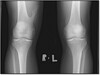

A

1. Open

2. Closed